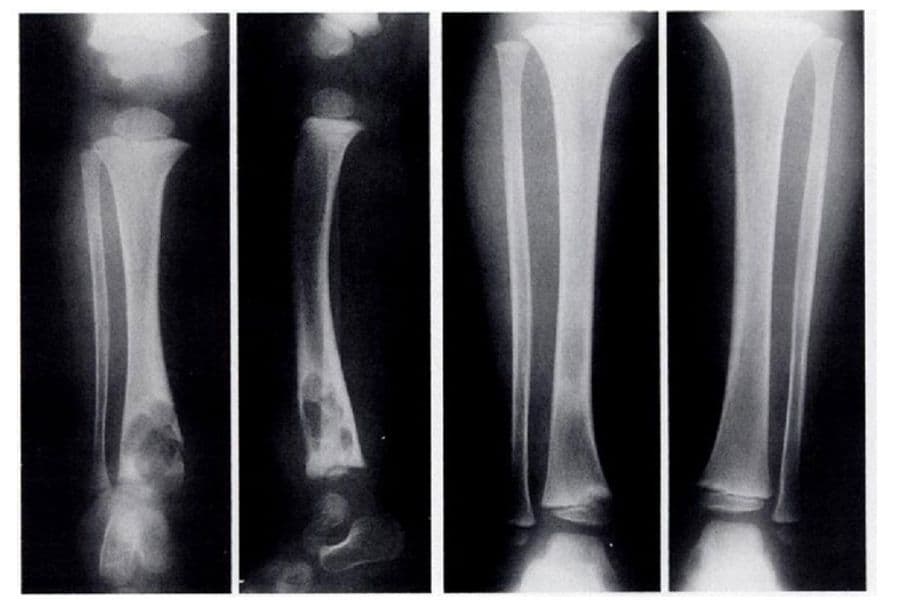

Bệnh lao xương là một bệnh nhiễm khuẩn ảnh hưởng đến hệ thống xương trong cơ thể, do trực khuẩn lao Mycobacterium tuberculosis gây ra.

Thông thường, bệnh lao xương không xuất hiện ngay từ đầu mà phát triển thứ phát sau khi bệnh nhân mắc lao phổi. Vi khuẩn lao từ phổi có thể di chuyển theo dòng máu hoặc hệ bạch huyết, sau đó khu trú tại một vị trí trong xương và gây bệnh.

Lao xương có thể xảy ra ở mọi lứa tuổi, nhưng phổ biến nhất trong khoảng từ 20 đến 40 tuổi. Cột sống là vị trí dễ bị ảnh hưởng nhất, tiếp theo là các khớp hông và gối. Trong cột sống, thân đốt sống và đĩa đệm thắt lưng là những khu vực thường bị vi khuẩn lao tấn công. Ngoài ra, bệnh cũng có thể xuất hiện ở các đốt sống cổ, xương cùng hoặc ít gặp hơn ở các vị trí như xương sườn, xương ức, xương chậu, xương dài, xương bàn tay hoặc bàn chân.

Lao xương thường tập trung tại một vị trí cụ thể, nhưng trong một số trường hợp, bệnh có thể xảy ra đồng thời ở nhiều vị trí, được gọi là lao xương đa ổ. Theo thống kê, 60-70% các ca bệnh lao xương tập trung ở cột sống, khoảng 10-15% xảy ra tại khớp gối, 5-10% ở khớp cổ chân, và 5% ở các khớp bàn chân.